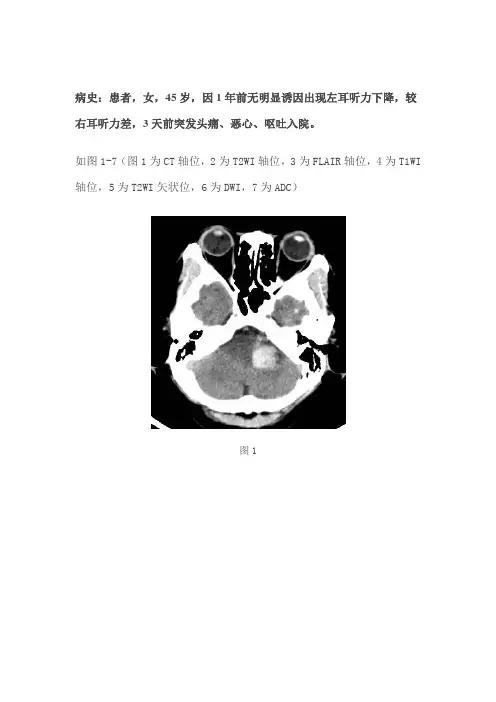

病史:患者,女,45岁,因1年前无明显诱因出现左耳听力下降,较右耳听力差,3天前突发头痛、恶心、呕吐入院。

如图1-7(图1为CT轴位,2为T2WI轴位,3为FLAIR轴位,4为T1WI 轴位,5为T2WI矢状位,6为DWI,7为ADC)图1图2图3图4图5图6图7基础解剖影像:图8图9图8-9为所示病例同层面轴位及矢状位正常T2WI图片,黄色箭头所示为正常耳蜗长T2信号,棕色箭头所示为正常听神经稍长T2信号,MRI 图像中骨质因不含自由水呈低信号,无法显示内听道骨质结构,蓝色箭头所示为桥小脑角池长T2信号,其内无异常信号影,其内线形低信号为听神经及小血管流空信号影。

图1图1所示为桥小脑角区CT轴位,可见左侧桥小脑角区混杂密度影(黄色箭头),以高密度为主,边缘见少许水肿低密度影(蓝色箭头)。